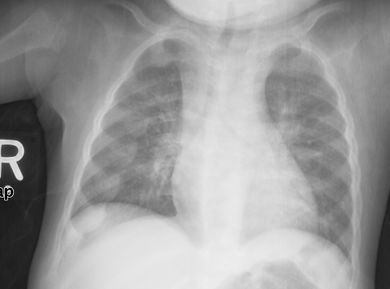

قد يكون الأطفال الصغار قد تقوست أرجلهم وتسمكوا في الكاحلين والمعصمين;[14] قد يصاب الأطفال الأكبر سنًا بالركبتين الروحاء.[11] تقوسات العمود الفقري من جنف حدابي أو قعس قطني قد تكون موجودة. قد تتشوه عظام الحوض . يمكن أن ينتج عن حالة تعرف باسم السبجة الرخادية ناتجة عن تشكل العقيدات على المفاصل الضلعية الغضروفية . يظهر هذا على شكل نتوء مرئي في منتصف كل ضلع في خط على كل جانب من الجسم. هذا يشبه إلى حد ما المسبحة ، مما أدى إلى ظهور اسمها. قد يؤدي تشوه صدر الجؤجؤي[11] إلى وجود تلم هاريسون.

تميل الأشعة السينية أو التصوير الشعاعي لمريض متقدم يعاني من الكساح إلى الظهور بطريقة كلاسيكية: الأرجل المنحنية (الانحناء الخارجي لعظم الساق الطويلة) والصدر المشوه. تحدث التغييرات في الجمجمة أيضًا مما يؤدي إلى ظهور "رأس مربع" مميز يُعرف باسم "caput quadratum".[15] تستمر هذه التشوهات في سن البلوغ إذا لم يتم علاجها تشمل العواقب طويلة المدى التقوس الدائم أو تشوه العظام الطويلة والظهر المنحني[16]